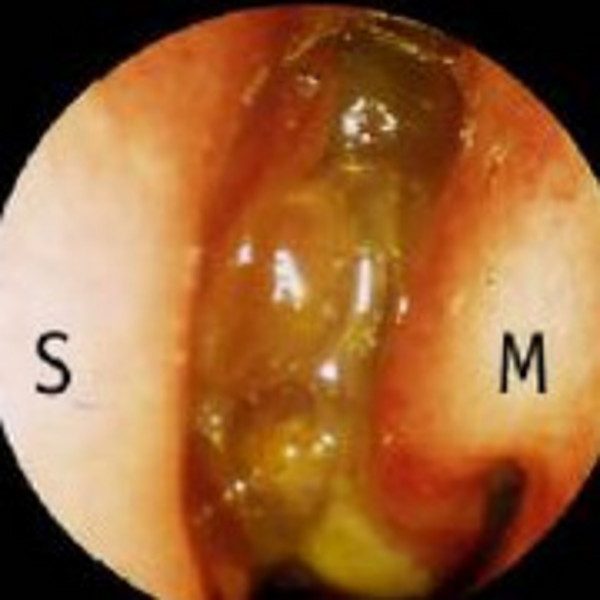

Polyposis nasi

Die Polyposis nasi ist eine Sonderform der chronischen Rhinosinusitis, deren Ätiologie noch weitgehend ungeklärt ist. Dabei handelt es sich bei den Nasenpolypen um gutartige Wucherungen der Nasen- und Nasennebenhöhlenschleimhaut, die vor allem Nasenatmungsbehinderung und Riechstörungen verursachen können.